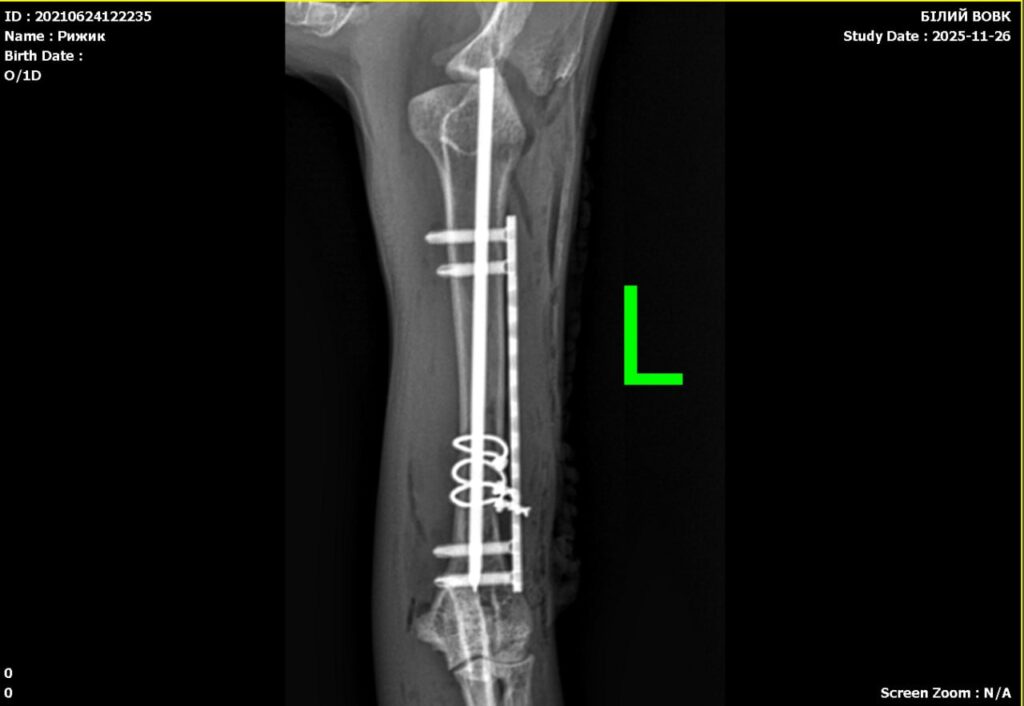

Ветеринарний лікар-травматолог займається діагностикою та лікуванням травм та ушкоджень кісток, м’язів, суглобів та сухожиль у тварин. Вони проводять огляд та діагностику травмованих тварин, виконують рентгенівське дослідження та інші необхідні діагностичні процедури, щоб визначити ступінь пошкодження тканин та з’ясувати, чи потрібне лікування. Огляд у ветеринарного травматолога може залежати від конкретної ситуації та травми, яку отримала тварина. Зазвичай, при прийомі до травматолога власник тварини повідомляє про обставини, що призвели до травми, та симптоми, які спостерігаються у тварини.

Ветлікар може провести огляд тварини, включаючи перевірку пульсу, температури тіла, стану шкіри та шерсті. Далі можуть бути проведені додаткові дослідження, такі як рентгенівське обстеження, ультразвукове дослідження, комп’ютерна томографія або магнітно-резонансна томографія, щоб отримати більш детальну інформацію про стан кісток, суглобів та м’язів тварини. Після діагностики травми, лікар-травматолог може призначити лікування, яке може включати ліки, фізіотерапію, хірургічні втручання або інші методи, залежно від характеру травми та стану тварини. Також, травматолог може надати власнику тварини рекомендації з догляду за твариною та профілактики травм. Хочемо зазначити, хоча ортопедичний огляд та огляд травматолога можуть включати схожі процедури, їх головна мета та спрямування різні.